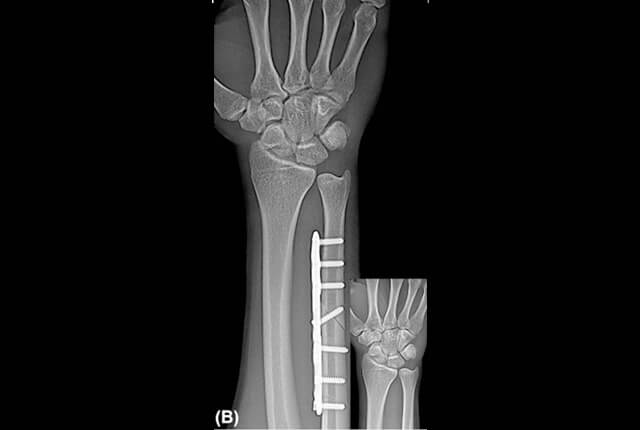

尺骨短縮術

plus varianceでDRUJ不安定性がない症例に行います。